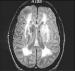

Kennen Sie Binswanger? Journal für Neurologie, Neurochirurgie und Psychiatrie 2002; 3 (2): 59-62 Volltext (PDF) Summary Abbildungen Keywords: Demenz, Morbus Binswanger, Neurologie Otto Ludwig Binswanger, 1852-1929, deutscher Nervenarzt, Jena. Zeitweise Mitarbeiter von Alois Alzheimer. Senile Demenz Binswanger Typ oder Morbus Binswanger wird meist für eine seltene Form der senilen Demenz gehalten. Mit zunehmender Verbreitung und häufigerer Anwendung von Neuroimaging-Methoden, wie Computertomographie (CT) und Magnetresonanz-Imaging (MRI), hat sich die Diagnose häufiger stellen lassen. Zahlreiche Namen sind diesem Zustand gegeben worden. 1894 hat Binswanger eine Form von Demenz erstmals als "encephalitis subcorticalis chronica progressiva" beschrieben und unterschied diese von der Neurosyphilis und anderen Formen. Er hat die Krankheit charakterisiert als Läsionen des subkortikalen Marklagers mit "schwerer Atheromatosis der Arterien", vergrößerten Ventrikeln und normaler Rinde. Der Begriff "Binswanger-Krankheit" wurde 1902 durch Alzheimer eingeführt. Der Begriff "subcortical arteriosclerotic encephalopathy" wird seit 1962 benutzt, und der Begriff "Multi-Infarkt-Demenz" hat seit 1974 weite Verbreitung gefunden. Als Überbegriff wird vaskuläre Demenz gebraucht und schließt sowohl den M. Binswanger als auch lakunäre thrombotische und embolische Gehirninfarkte mit ein. Der Begriff "senile dementia Binswanger type" wurde 1987 empfohlen. |